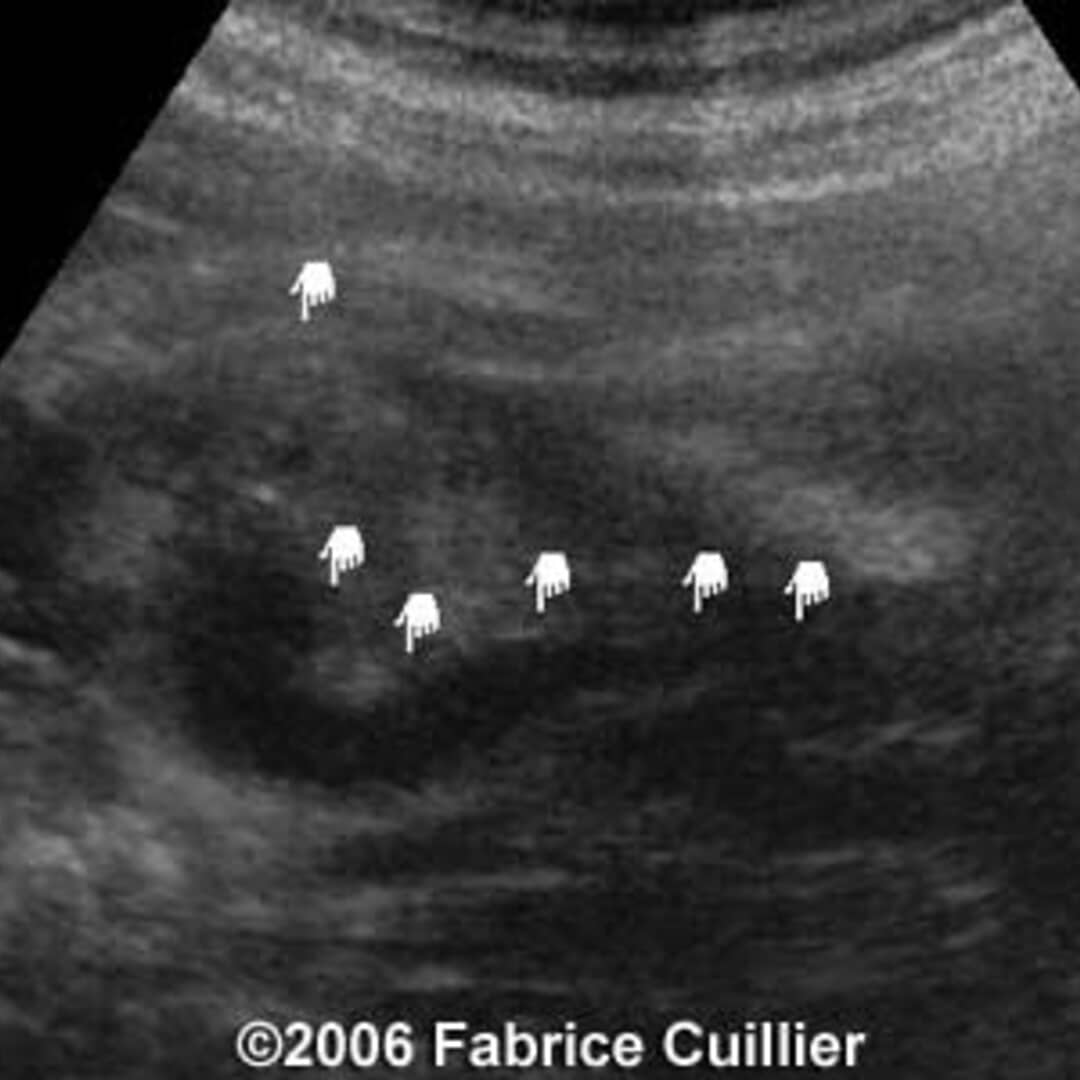

Per megauretere in campo medico, si intende un'anomalia che riguarda la grandezza dell'uretere che risulta più ampio della normale condizione.